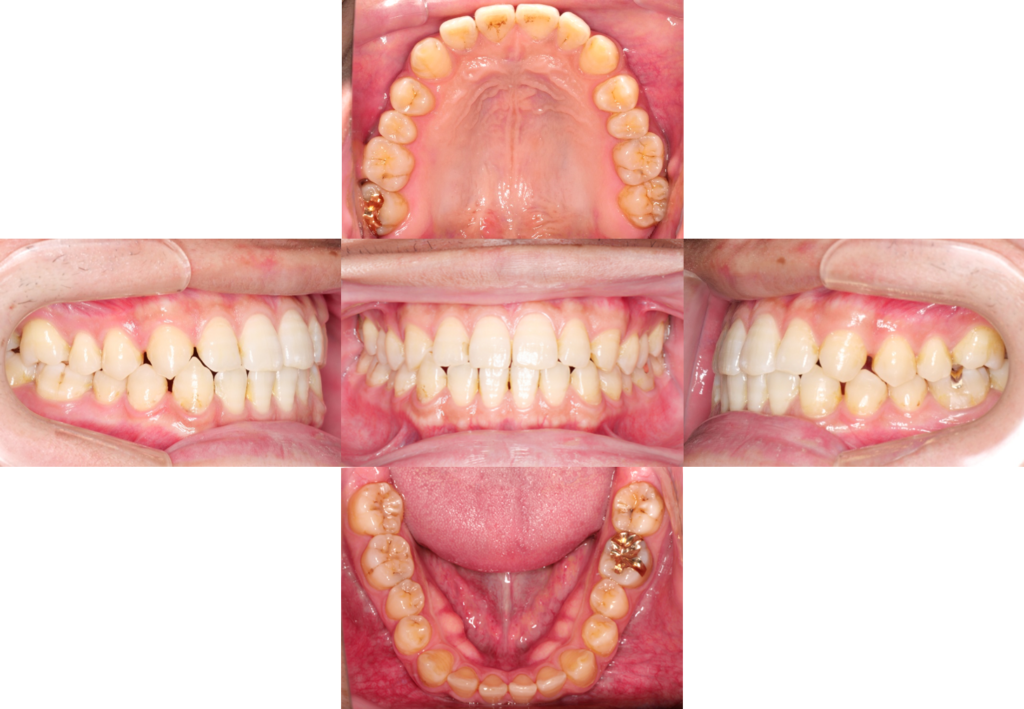

①口腔内写真

虫歯の有無や、歯の形態、歯茎の状態などレントゲンだけでは確認できない内容を確認します。